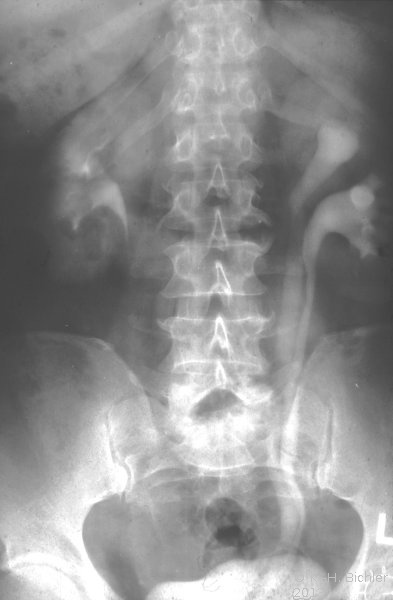

Entstehen im Zusammenhang mit dem fehlgebildeten Anteil zumeist durch Harnstau (z.B. Harnsteinbildung) bzw. Infekt. Die entsprechende Symptomatik führt dann zur Entdeckung und der operativen Behandlung mit Entfernung des fehlgebildeten Nierenanteils (Abbildung 4) (

Fehlbildungen des Harnleiters). Die Doppelbildungen des Harnleiters können bei Steinbildung insbesondere in einem Ureterfissus Schwierigkeiten bereiten.